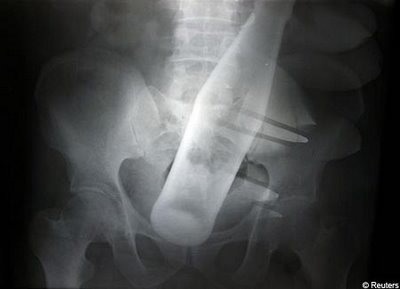

![]() |

| Một khẩu súng mắc kẹt ở khu vực xương chậu của nạn nhân. |